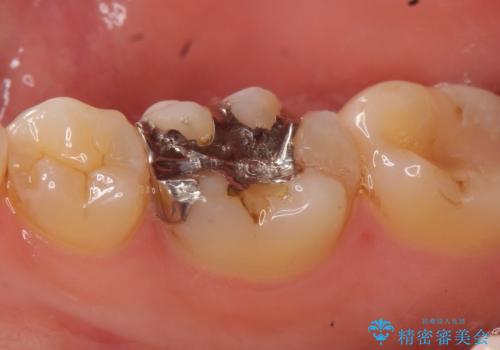

- 右下の銀歯が気になるといらっしゃった方の症例です。

右下6番目の銀歯を除去後、セラミックインレーによる修復を行いました。